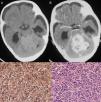

Los quistes aracnoideos intracraneales constituyen una patología frecuente en la edad infantil y su tratamiento quirúrgico se realizará en función de su sintomatología y su localización. Habitualmente se trata de lesiones únicas, aunque pueden asociarse a otras patologías tanto malformativas como tumorales. Presentamos el caso clínico de un varón recién nacido diagnosticado de un quiste aracnoideo de la cisterna cuadrigeminal que fue tratado mediante endoscopia. En el postoperatorio, ante un empeoramiento neurológico se diagnosticó un meduloblastoma de cerebelo que no se evidenciaba en los estudios neurorradiológicos previos y del que se realizó una extirpación parcial. Dada la edad del paciente y el pobre pronóstico, no se realizó tratamiento oncológico. La asociación de un meduloblastoma de cerebelo y un quiste aracnoideo es excepcional, y hasta donde podemos conocer únicamente existe en la bibliografía un caso similar.

Arachnoid cysts are very common lesions in paediatric patients, with treatment depending on their location and symptomatology. They are usually solitary cysts but may be associated with other central nervous system diseases such as tumours and congenital deformities. We describe the case of a neonate diagnosed with an arachnoid cyst of the quadrigeminal cistern treated by endoscopy. After the operation, the child's condition worsened; a CT scan revealed a midline posterior fossa tumour not visible in the preoperative neuroradiological tests. The tumour, a medulloblastoma, was partially removed. Given the child's age and the poor prognosis, oncological treatment was not undertaken. The association between medulloblastoma and arachnoid cyst is very rare, and we could find only one such case in the literature.